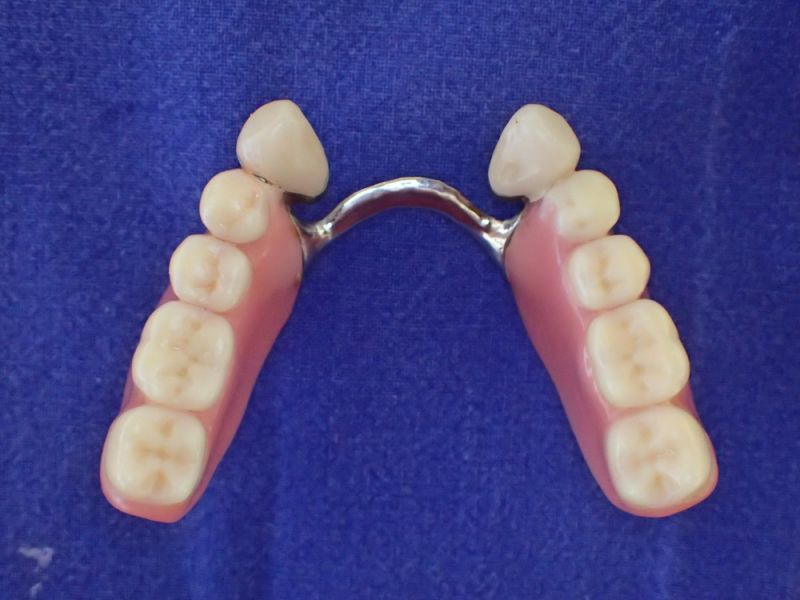

Die aktuelle Arbeit war unverändert 15 Jahre in Funktion.

Vorhandene Teleksoparbeit, seit 15 Jahren im Munde der Patientin und aktuelles Übersichtsröntgenbild vor der Entfernung des Zahnes 33